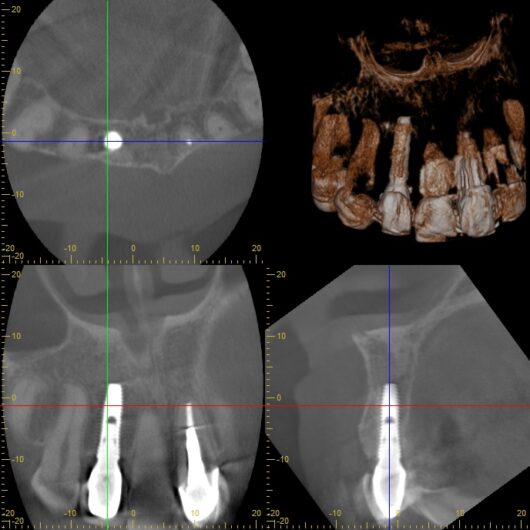

「前歯の違和感」という主訴に対して、まずは客観的な評価が必要です。今回、以下の検査を実施しました。

検査の結果、インプラント周囲の骨の状態、インプラント体の位置、周囲組織の状態など、すべてにおいて問題は認められませんでした。これは、8年間適切にメインテナンスを継続してきた成果と言えるでしょう。